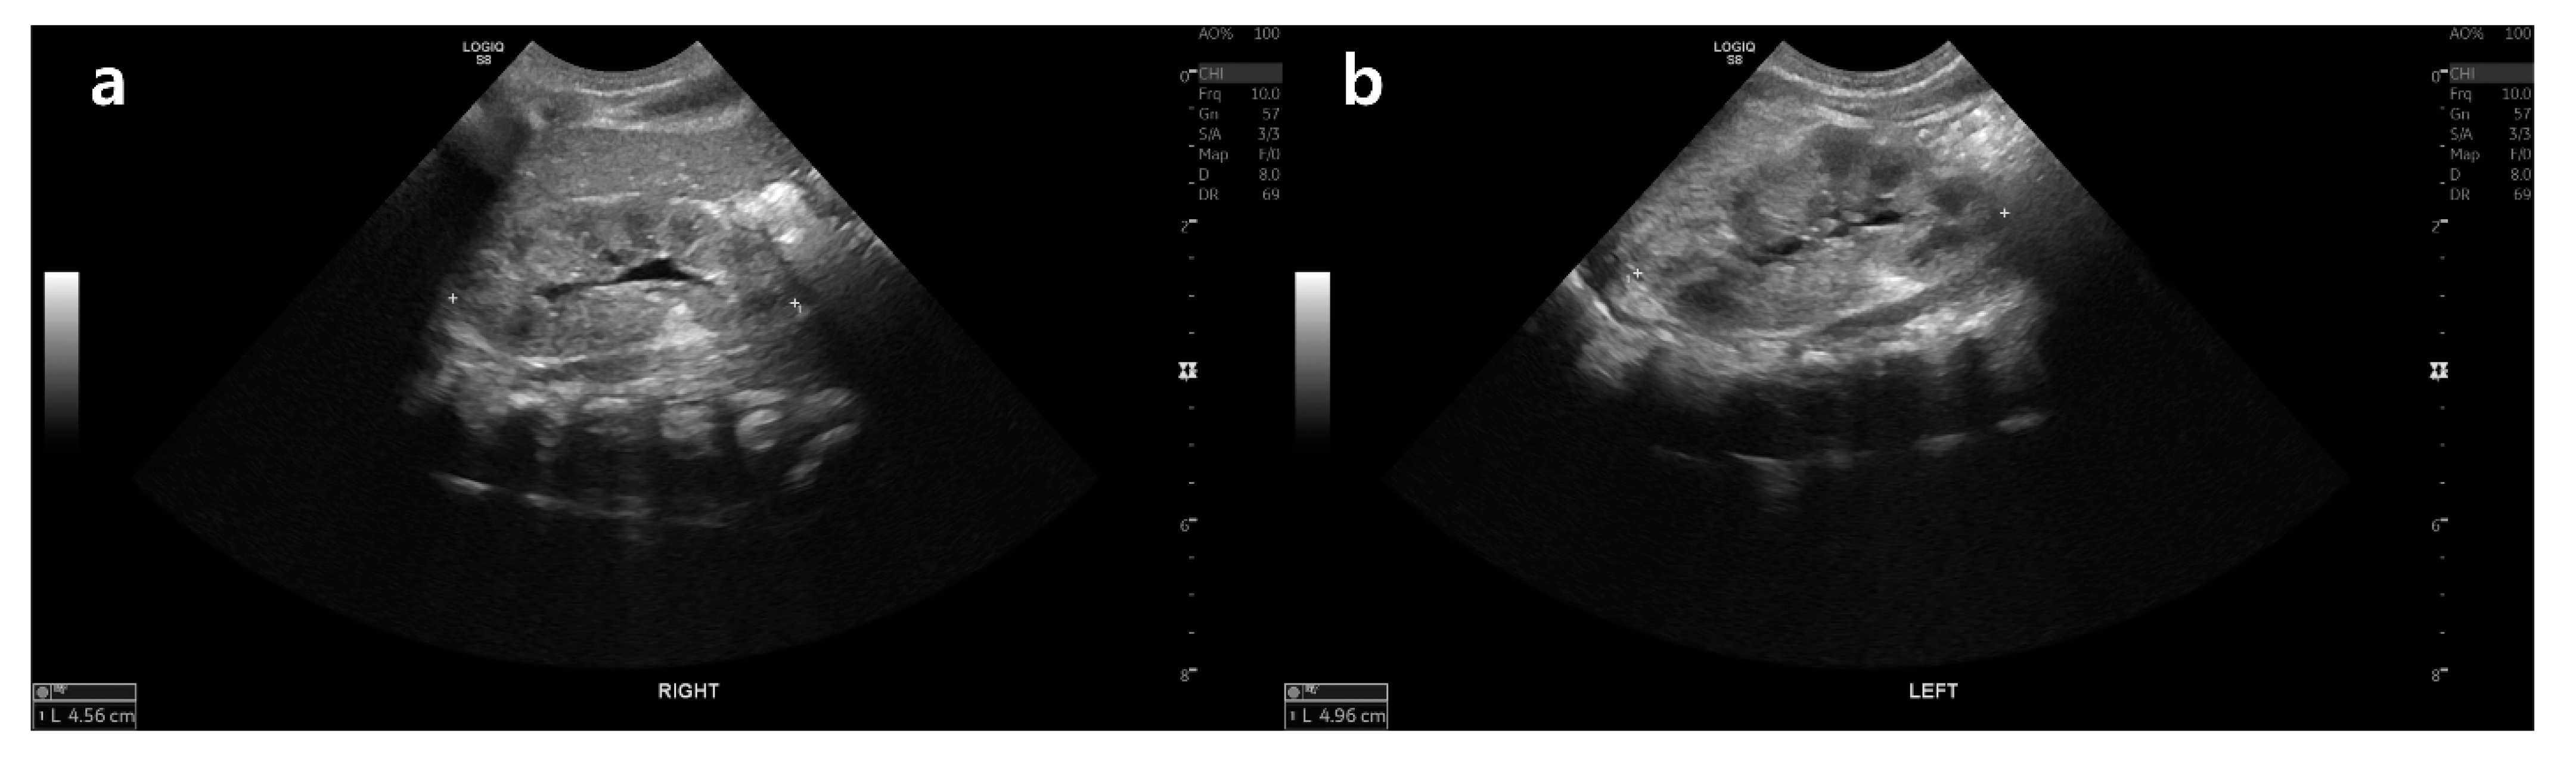

2. Case Presentation